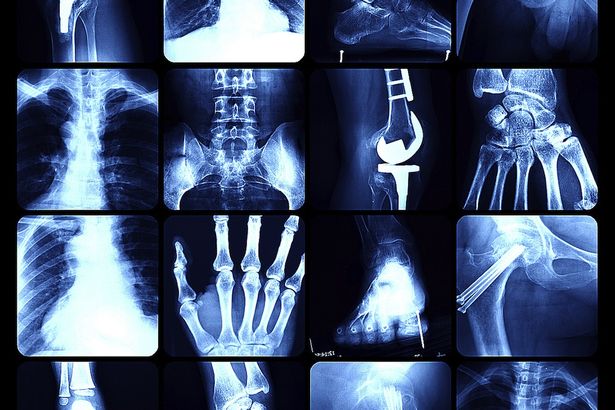

Η Οστεοπόρωση είναι η μείωση της οστική πυκνότητας των οστών και μπορεί να οδηγήσει σε κατάγματα και τραυματισμούς.

Η οστεοπόρωση, ICD-10 M80-M82, είναι μια συστηματική νόσος του σκελετού, που χαρακτηρίζεται από χαμηλή οστική μάζα και διαταραχή της μικροαρχιτεκτονικής του οστού, με αποτέλεσμα τη μειωμένη μηχανική αντοχή των οστών και τον αυξημένο κίνδυνο καταγμάτων. Ο κίνδυνος να υποστούν οστεοπορωτικό κάταγμα οι γυναίκες είναι 16% για κάταγμα σπονδύλου, 15% για κάταγμα καρπού και 16% για κάταγμα ισχίου.

Η έγκαιρη διάγνωση της οστεοπόρωσης γίνεται με τη μέτρηση της οστικής πυκνότητας. Η εξέταση αυτή πραγματοποιείται σε ολόκληρο το σώμα, αλλά, κυρίως, στις καταπονημένες περιοχές, όπως στον αριστερό μηρό και στην οσφυϊκή μοίρα της σπονδυλικής στήλης.

Υπάρχουν μηχανήματα, που έχουν την δυνατότητα μέτρησης της οστικής μάζας με υψηλή ακρίβεια και πολύ μικρή ακτινοβολία. Θα πρέπει να ξαπλώσετε ντυμένος πάνω σε ένα ειδικό κρεβάτι, για περίπου 15 λεπτά της ώρας, ενώ θα γίνεται στα οστά σας ακτινογραφία. Η δόση αυτής της ακτινογραφίας είναι πάρα πολύ μικρή – περίπου η ίδια με εκείνη όταν είστε όλη την ημέρα στον ήλιο. Η τεχνική αυτή ονομάζεται “διπλής ενέργειας απορροφησιομετρία με ακτίνες Χ” (Dual Energy X-ray Absorptiometry, DEXA).